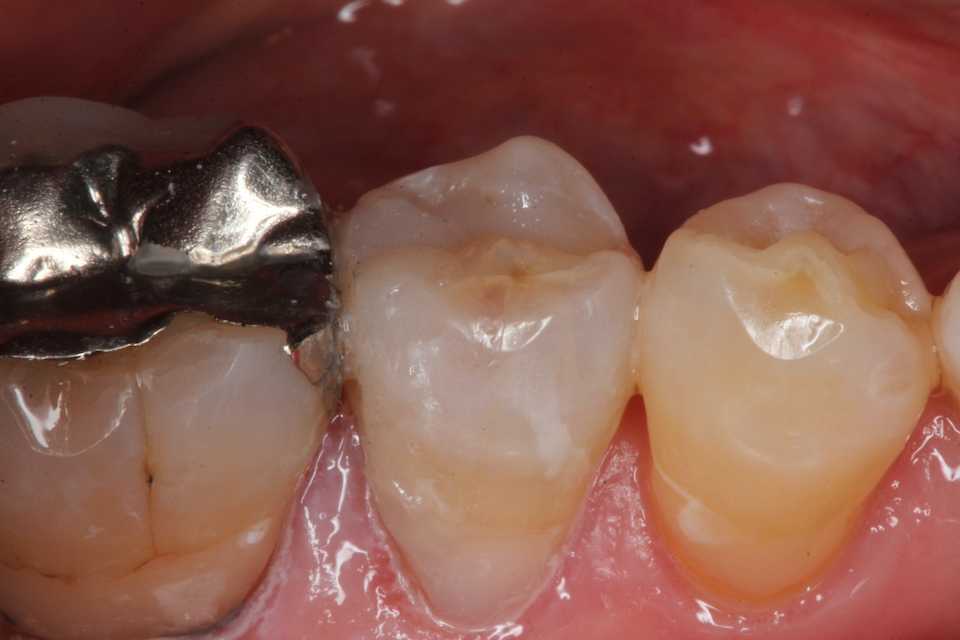

50代女性、右下5、インレー2次カリエス

では時系列でどうぞ